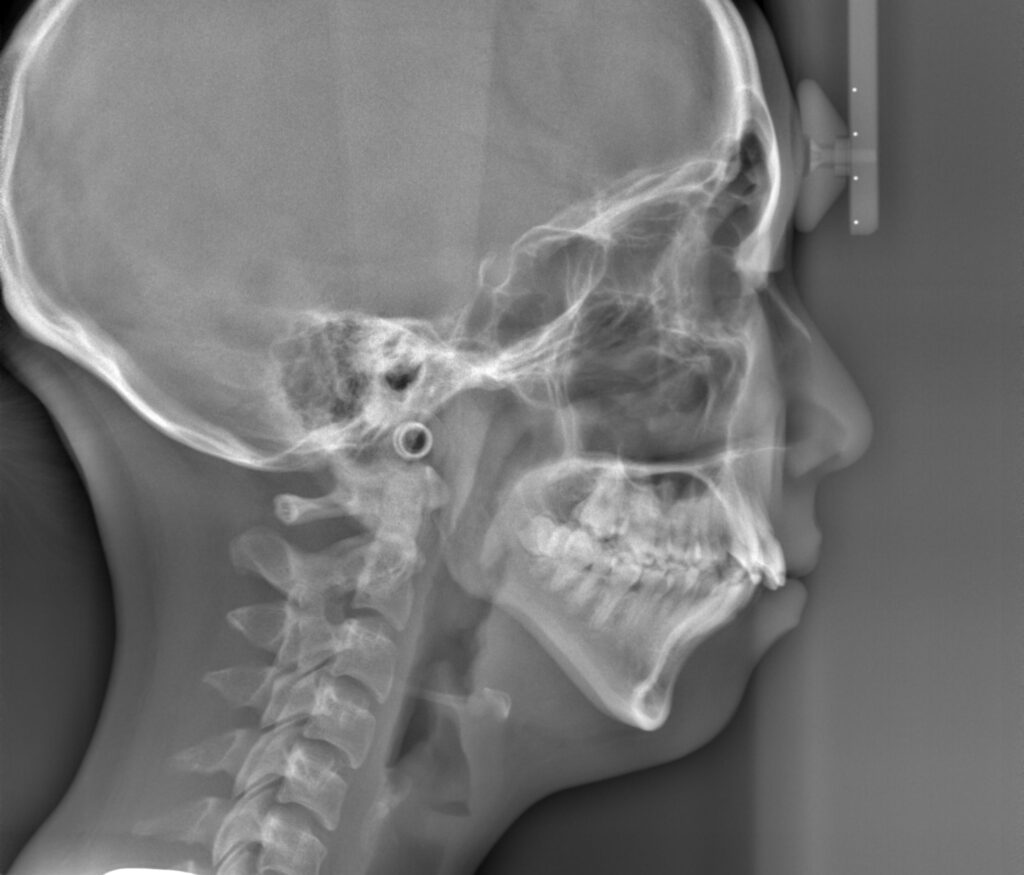

④検査ーレントゲン撮影ー

レントゲン撮影も、緊張しましたが先生が優しく声を掛けながら撮影してくださるので安心です!😄

診断では、撮影した写真やレントゲンを先生が分析し、細かい治療計画を立ててくださいます!